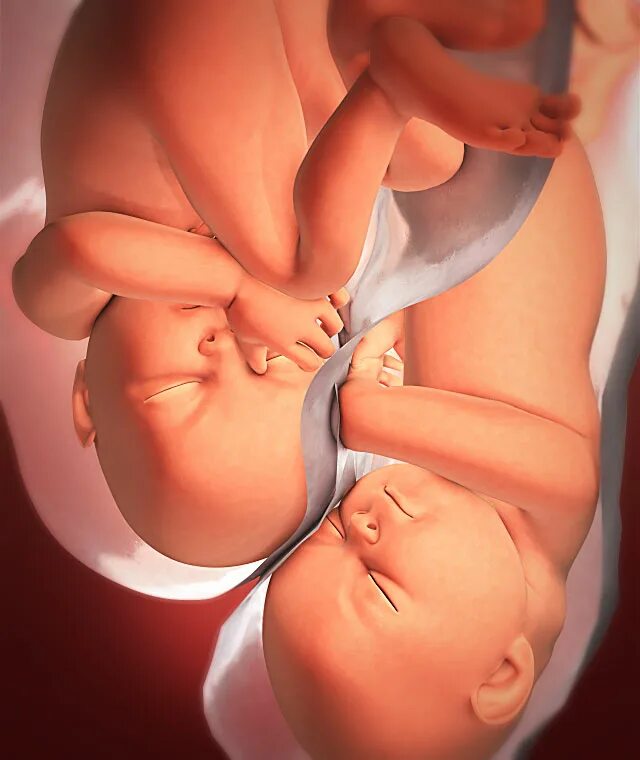

Ребенок 36 недель беременности в животе